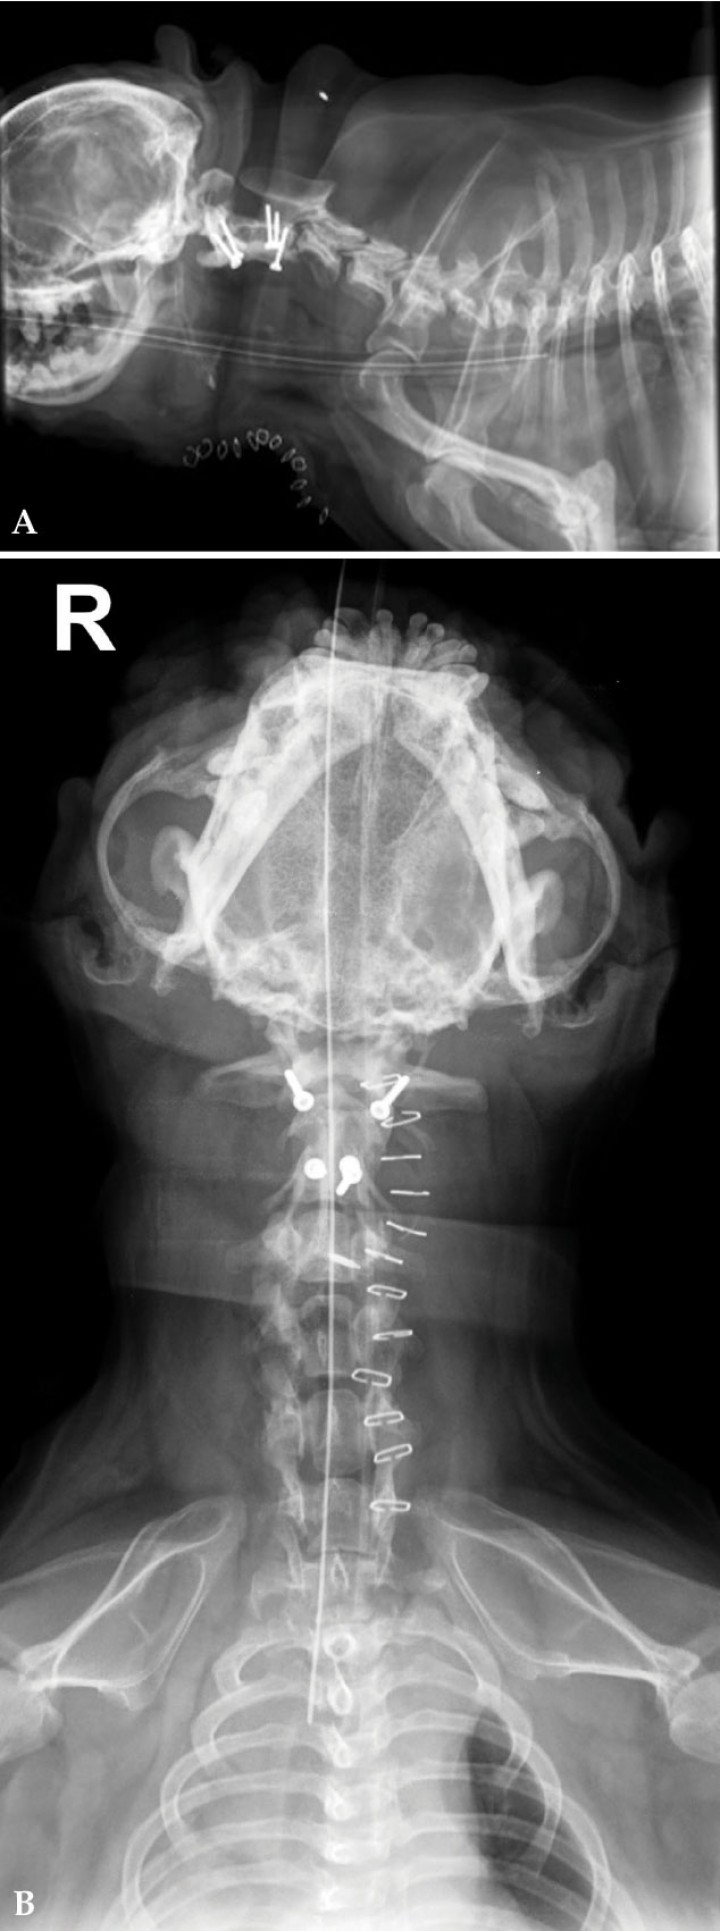

El paciente aquí descrito presentó una recidiva de la luxación atlantoaxial. La primera cirugía se realizó mediante un abordaje dorsal con suturas. Ocho años más tarde, se realiza una fijación ventral. Se utiliza un abordaje ventral medio estándar centrado en la región C1-C2 hasta localizar la articulación atlantoaxial. Se legra el cartílago articular de C1-C2 mediante el uso de la cureta quirúrgica hasta exponer el hueso subcondral. Se coloca un primer tornillo en el tercio posterior del cuerpo del axis y se reduce la compresión del diente del axis sobre la médula espinal mediante una leve tracción caudal de C2. Tras reducir la subluxación, se colocan cuatro tornillos corticales de 2 mm de diámetro y 14 mm de longitud (Aesculap; Instrumevet; Granollers) en el cuerpo de C1 y C2. Dos tornillos se sitúan en el arco ventral del atlas dorsolateralmente y orientados hacia los pedículos, y dos en el cuerpo del axis, angulados 30-40 grados dorsolateralmente. Posteriormente, se añade polimetilmetacrilato con gentamicina (Palamed G; Heraeus; Boadilla del Monte) en fase semilíquida y se aplica a la superficie vertebral ventral para envolver todos los tornillos. El moldeado del cemento se realiza a la vez que se lava profusamente la zona con suero fisiológico salino estéril. La incisión cervical se cierra por planos de manera rutinaria. La cirugía transcurre sin incidencias y se realizan radiografías postquirúrgicas que demuestran una correcta posición de los implantes y reducción de la subluxación atlantoaxial (Fig. 2).

<p>Radiografía post-quirúrgica. (<strong>A</strong>) Lateral derecha. (<strong>B</strong>) Ventrodorsal. Se visualiza la estabilización atlantoaxial mediante tornillos y polimetilmetacrilato con gentamicina. R: derecha.</p>

Radiografía post-quirúrgica. (A) Lateral derecha. (B) Ventrodorsal. Se visualiza la estabilización atlantoaxial mediante tornillos y polimetilmetacrilato con gentamicina. R: derecha.